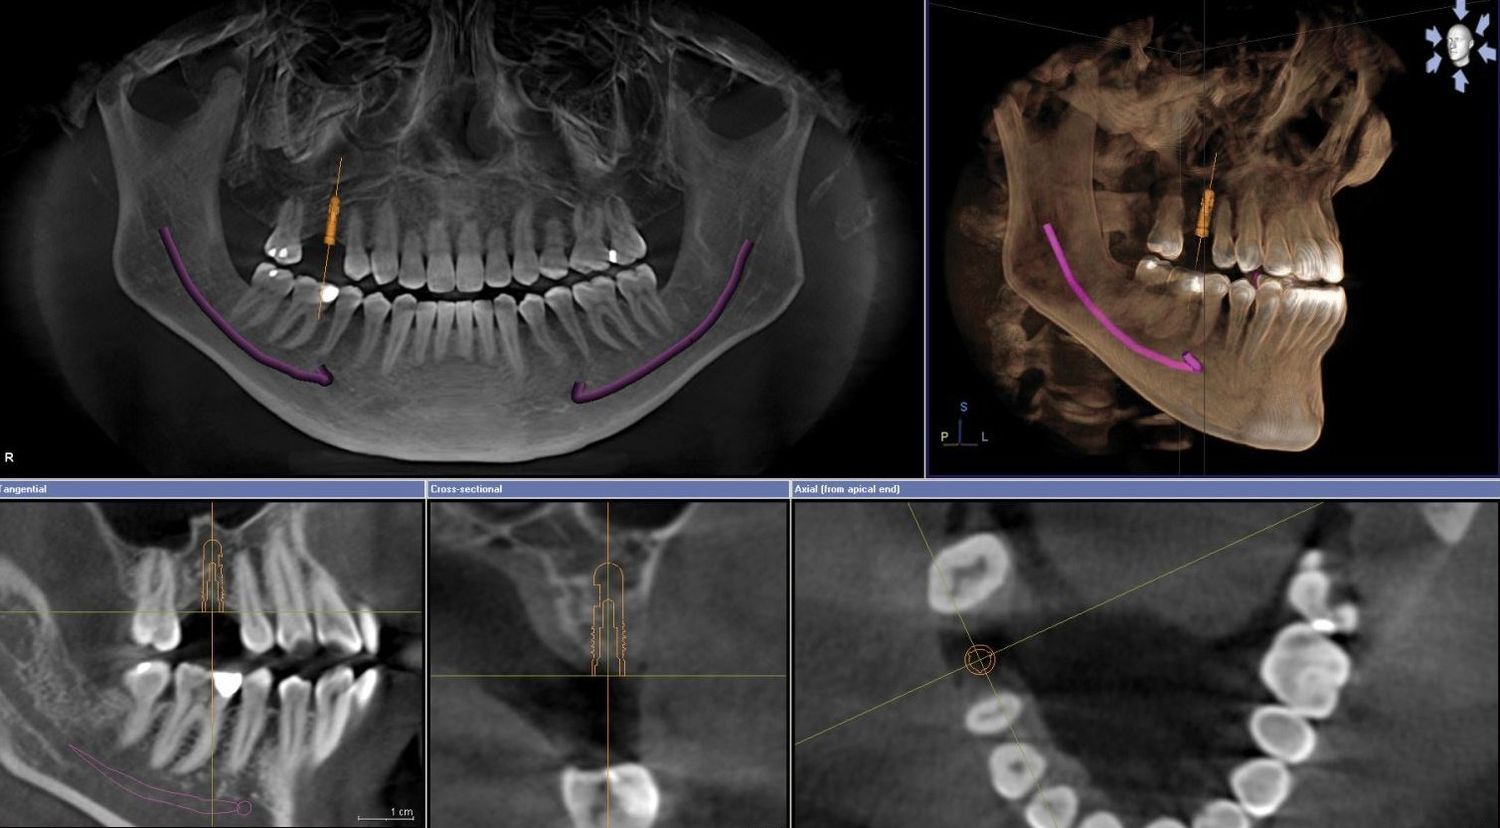

Рентгеновский снимок является основным инструментом стоматолога в постановке правильного диагноза . Полученные при КТ объемные снимки позволяют специалисту увеличить, повернуть и исследовать со всех сторон и на разной глубине интересующую область

Рентген челюсти в 3D понадобится пациенту, проходящему лечение у таких специалистов: имплантолог, ортодонт, стоматолог-хирург . Ортопантомограмма в 3D-формате выявляет дефекты зубного ряда и начальные стадии патологического процесса .

И другие важные вопросы о 3D-снимках в стоматологии . Современная стоматология немыслима без компьютерной томографии . Ее назначают перед имплантацией, терапевтическим, ортодонтическим лечением зубов и протезированием .